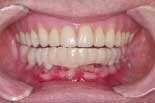

When the final restorations are received from the lab, they are inspected on the mounted models (figures 26 and 27). The final restoration is placed in the mouth and screwed in place. The access holes are filled with Clip, pink opaque composite and tooth-colored composite (figures 28 and 29). Final occlusal adjustments are made and esthetics confirmed (figure 30).